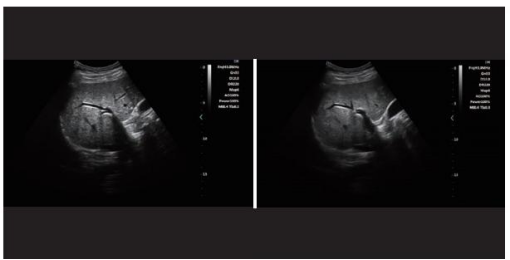

Ultrasound-1 .png

Harmonic imaging technology(THI)

It improves image clarity by improving tissue contrast resolution,  spatial   resolution,and eliminating near-field artifacts.It is mainly used forthe diagnosis of cardiovascular and abdominal diseases.It plays an important role in evaluating the lesion area and boundary division of patients with imaging difficulties. Thetechnology has been fully approved by clinicians.

Harmonic technology retains the second harmonic signal to the greatest  extent based on removing the fundamental signal,which increases the signal strength by more than 30% compared with the traditional signal  processing,reduces noise and artifacts,and improves the contrast resolution of tissue images.